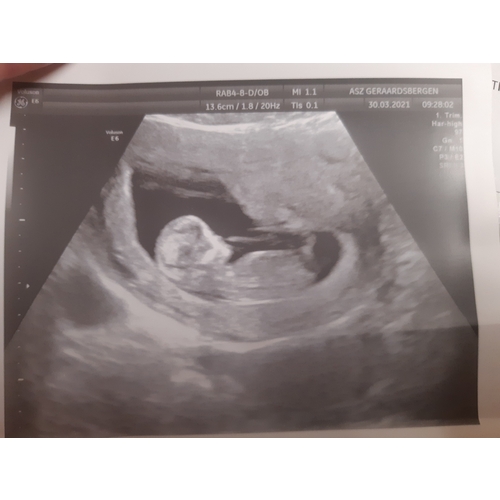

13 weken ongeveer op de foto en bijmij is het een meisje en ik denk een jongen bij jou 😊 en bijmij duurde het 7 dagen. Had het via email gekregen toen

Dinsdagochtend bloed geprikt en de week erna donderdagmiddah resultaat op Cozo. Wel paasweekend ertussen! Echo van 11 weken en 6 dagen. We krijgen een meisje! 💕💕

Ik pas uitslag na 12 dagen en zelf moeten bellen. En ik denk een jongen 😊